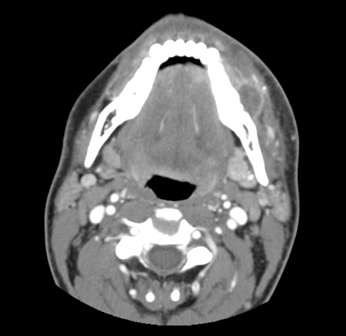

The results of contrast-enhanced maxillofacial computed tomography (CT) scans revealed an odontogenic facial soft-tissue abscess (Figures 1-3). There were partially missing first and second left mandibular molars with an adjacent rim-enhancing perimaxillary hypodensity consistent with a periapical abscess. Regional cellulitis and lymphadenopathy were present.

Figure 1. Axial contrast-enhanced CT showing facial swelling and cellulitis with a rim-enhancing fluid collection along the left lateral mandible.